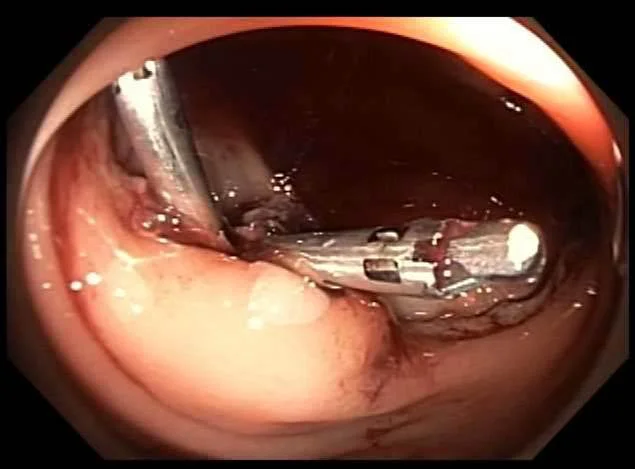

Bleeding vessel seen on flexible sigmoidoscopy

Clips placed successfully.